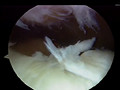

Knee 1

Professional knee operation.